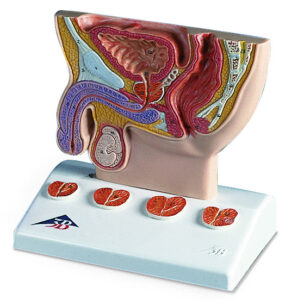

Female Pelvis Skeleton Model – 3 part

This life size three part model represents an original cast of a bony female pelvis and shows all the details of the following anatomical structures: Two hip bones, the pubic symphysis, the sacrum and the coccyx, the fifth lumbar vertebra with intervertebral disc.

A midsagital section through the fifth lumbar vertebra, sacrum and coccyx, allow both halves of the pelvis to be disassembled revealing a part of the cauda equina in the vertebral canal. The left half of the fifth lumbar vertebral body is removable.

Female Pelvis Skeleton Model - 3 part

This life size three part model represents an original cast of a bony female pelvis and shows all the details of the following anatomical structures: Two hip bones, the pubic symphysis, the sacrum and the coccyx, the fifth lumbar vertebra with intervertebral disc.

A midsagital section through the fifth lumbar vertebra, sacrum and coccyx, allow both halves of the pelvis to be disassembled revealing a part of the cauda equina in the vertebral canal. The left half of the fifth lumbar vertebral body is removable.

- Weight: 1.38 kg

- Dimensions: 19 x 27 x 19 cm